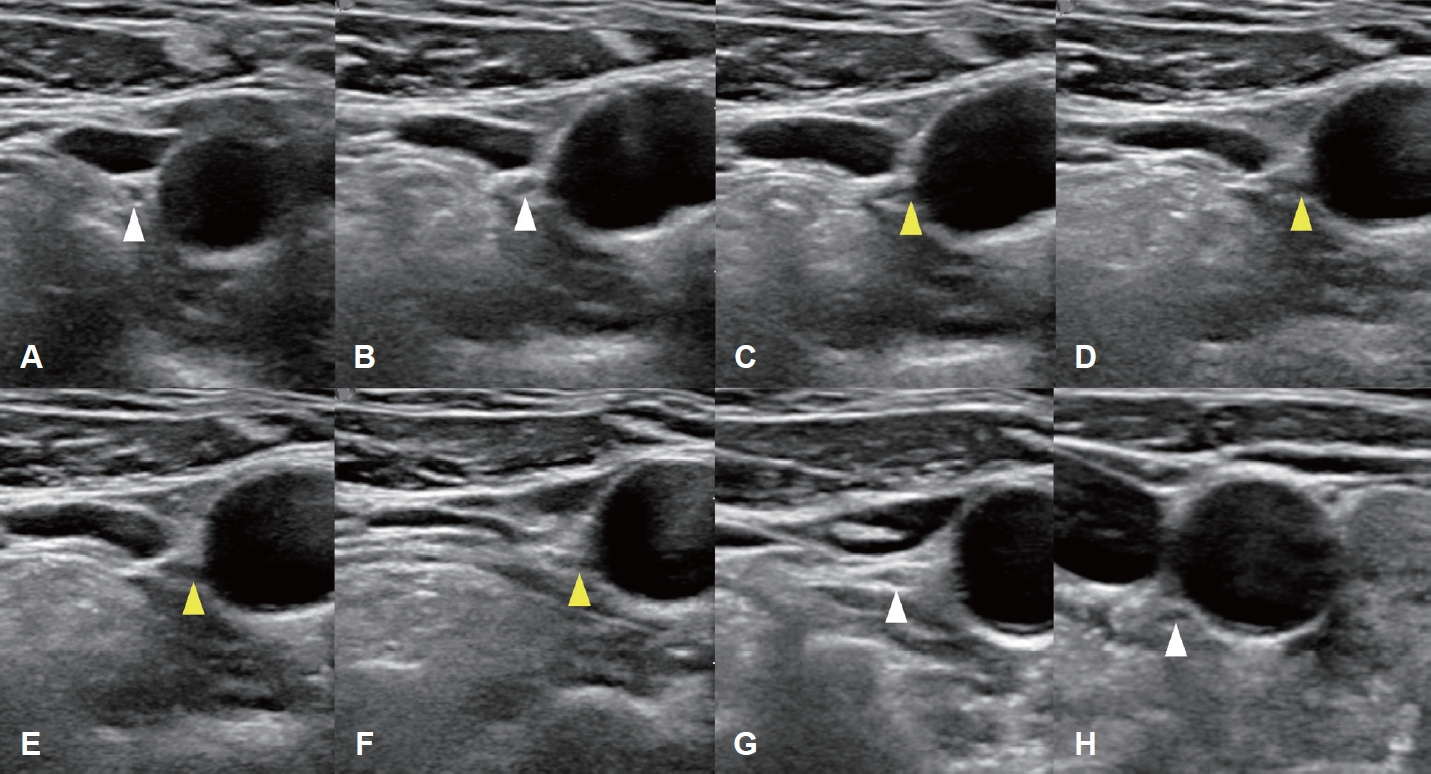

증 례78세 여성이 한 달 전부터 발견된 전방 경부 종괴를 주소로 내원하였다. 신체검사 및 촉진 결과 갑상선 종괴가 의심되었고, 수일 후 시행한 초음파 검사에서 좌측 협부에 44 mm 크기의 갑상선 결절이 확인되어 중심바늘생검(core needle biopsy)을 시행하였으며, 갑상선 유두암(papillary thyroid cancer)이 진단되었고 초음파와 조영증강 갑상선 CT (thyroid CT)를 시행하였으며 수술 전 임상병기는 cT3bN0으로 판정되었다. 경부 초음파 검사는 고해상도 초음파 기기(EPIQ7, Philips Healthcare)와 5-12 MHz 선형탐촉자를 사용하여 갑상선 및 두경부 초음파에 숙련된 영상의학과 전문의에 의해서 수행되었다. 조영증강 갑상선 CT는 갑상선암 진단에 최적화된 대한갑상선영상의학회에서 제시한 표준검사기법으로 수행되었으며[1], 조영제 주입 후 35초 시점에 영상이 획득되었고, 2 mm 절편 두께로 횡단면, 관상면, 시상면 영상이 재구성되었다. 갑상선 전절제술 및 중앙 경부절제술을 계획하였고 thyroid CT에서 우측 이상 쇄골하동맥이 확인(Fig. 1)되어 비반회후두신경 가능성을 고려하여 비반회후두신경 평가를 위해 수술 전 경부 초음파를 추가로 시행하였다. 비반회후두신경의 초음파 평가는 설골 부위에서부터 미주신경을 초음파로 확인한 후에 미주신경을 하방으로 연속적으로 추적하여 미주신경에서 내측으로 분지되는 신경 유무를 평가하였다. 본 증례에서는 초음파 검사에서 갑상연골 높이의 미주신경으로부터 직접 분지되어 총경동맥 후방 쪽으로 주행하는 저에코의 신경 가지를 확인하였다(Fig. 2). 이후 예정된 수술을 시행하였으며, 피부 절개 후 갑상선 검체를 박리하는 과정에서, 한국 표준화된 신경모니터링 방법2)을 사용하여 수술 중 신경모니터링을 적용하였고, 모니터는 잘 작동하였다. 수술 시 type II 비반회후두신경을 확인하였으며(Fig. 3), 수술 중 신호손실(loss of signal) 등의 문제는 없었으며, 수술 직후 및 외래 추시 시 내시경 검사에서 성대마비는 관찰되지 않았으며(Fig. 4), 입원 중 특이 합병증이 관찰되지 않았다. 병리 결과는 유두암, 고전형(classical type), 단일 결절(3.9×3.0×3.0 cm), 갑상선 외 침범(macroscopic extrathyroidal extension) 및 좌측 6번 경부 구획에서 한 개 림프절에서 미세 림프절 전이가 확인되었다. 림프혈관 침윤, 신경 침윤, 외측 절제면 침범은 없었다. 환자는 내분비내과에서 정기적인 추적 검사를 진행하며, 방사선 요오드 치료(radioactive iodine)를 권고하였으나 환자의 의사에 따라 시행되지 않았다. 내분비내과에서는 권장했지만, 환자는 이를 거부하였다. 추적 검사에서는 T3, T4, 갑상선자극호르몬, 갑상선글로불린 등을 포함한 갑상선기능 검사 및 화학검사에서 정상 범위 수치를 보였다.

저자들은 수술 전 초음파를 통해, 미주신경으로부터 비반회후두신경이 직접 분지되는 경우, 미주신경의 원래 주행 경로를 따라 진행함과 동시에 비반회후두신경 역시 동시에 한 초음파 화면에 시각화할 수 있을 것으로 예상하였다. 실제 영상에서는 비반회후두신경으로 추정되는 가지는 관찰하였으며, 그 아래로 연속되는 미주신경의 본래 주행 경로는 확인하였다. 다만, 분지를 낸 미주신경의 직경이 분지를 내지 않은 미주신경보다 유의하게 작다는 점을 고려할 때, 다른 환자에서 시행 시 비반회후두신경의 분지를 시각화는 가능할 수 있으나, 분지 이후의 미주신경은 초음파상으로 탐지하지 못할 가능성이 있다[13]. 또한 우리는 비반회후두신경에 여러 유형이 있다는 점을 고려해야 한다. 고위형 비반회후두신경(type I)은 미주신경 줄기에서 직각으로 발생하여 짧은 경로로 횡단하며 후두기관분기(laryngotracheal junction)에 도달한다. 저위형 비반회후두신경(type II)은 미주신경 줄기에서 발생하여 기관식도홈(tracheoesophageal groove)에 도달하기 전에 상외측으로 오목한 형태를 보인다[14]. Type 1 비반회후두신경의 경우 type 2인 경우와 비교하였을 때 상갑상동맥에 비해 비교적 높은 위치에서 분지하여 수술 중 상갑상동맥 결찰 시 비교적 손상 가능성이 적을 수 있으나, type 2의 경우 상갑상 동맥과 나란히 주행하거나 교차하여 진행하거나 하갑상동맥과 인접하여 주행한다. 수술 전 유형을 확인할 수 있다면 수술 중 비반회후두신경의 손상 예방에 큰 도움이 될 수 있을 것이라 생각된다. 따라서 이러한 해당 유형들에 따라 수술 전 초음파를 통한 미주신경 및 비반회후두신경의 추적 양상에 영향을 줄 수 있는지, 해당 유형들을 미리 예측 가능한지에 대해 통계적 데이터를 수집하는 연구가 필요할 것으로 보인다. 다만, 본 증례의 경험에 기초하면 비반회후두신경은 경동맥 후방부 위치까지 구분이 가능하였고, 경동맥에서 갑상선으로 주행하는 신경은 발견되지 못했기 때문에 t ype 1과 type 2를 구분하는 것은 어려울 것으로 판단되며 초음파를 통한 경부 주요 신경을 정확히 잔단할 수 있는 숙련된 의사에 의해서만 가능하기 때문에 임상적용에 제한적 요인이 있을 것으로 판단되나, 이에 대한 추가적 연구가 필요할 것이다. 또한 CT 촬영에서 우측이상쇄골하동맥이 확인된 경우 비반회후두신경의 존재 가능성이 매우 높기 때문에 본 증례에서 시행한 정밀 초음파를 우측 이상쇄골하동맥이 확인된 경우 추가로 시행하여 수술 전 비반회후두신경의 type을 예측할 수 있을 만한 케이스를 누적할 수 있도록 검사를 제안하는 바이다. Type 1 비반회후두신경의 경우 상갑상동맥의 인접한 상방에서 주행하기에 type 2 비반회후두신경과 감별해 볼 수 있는 포인트가 될 수 있을 것이다.

Fig. 1.Preoperative enhanced thyroid CT images of an ARSA. A: Axial enhanced CT shows the ARSA (arrow) arising from the aortic arch and coursing posterior to the esophagus. B: Coronal enhanced CT shows the retroesophageal ARSA (arrow). ARSA, aberrant right subclavian artery. Fig. 2.Serial ultrasonographic tracking images of the NRLN obtained using a 5–12 MHz linear-array transducer. A-F: A series of transverse ultrasound images arranged in craniocaudal order shows the suspected right NRLN (yellow arrowheads). A and B: The right vagus nerve (white arrowheads) is visualized between the IJV and CCA at the level of thyroid cartilage. C and D: A nerve branch is seen arising directly from the right vagus nerve. E and F: The nerve branch courses horizontally and medially toward the CCA. G and H: The descending vagus nerve (white arrowheads), separated from the NRLN, is seen at the level of the cricoid cartilage and thyroid gland. This direct, non-recurrent path from the right vagus nerve at the level of the larynx is highly suggestive of an NRLN. NRLN, non-recurrent laryngeal nerve; IJV, internal jugular vein; CCA, common carotid artery. Fig. 3.Intraoperative identification of the NRLN. The right NRLN is indicated by a yellow arrowhead during thyroidectomy. The green arrowhead indicates the electrode positioned on the perichondrium of thyroid cartilage. NRLN, non-recurrent laryngeal nerve. Fig. 4.Postoperative laryngoscopy showing vocal cord function. A: Laryngoscopy on POD 11 complete abduction during inspiration. B: Laryngoscopy on POD 11 also shows complete adduction during phonation. C: Laryngoscopy on POD 4 years reveals improved vocal cord movement. Both vocal cords are fully abducted during inspiration. D: Laryngoscopy on POD 4 years shows full adduction of both vocal cords during phonation. POD, postoperative day. REFERENCES1. Ha EJ, Chung SR, Na DG, Ahn HS, Chung J, Lee JY, et al. 2021 Korean thyroid imaging reporting and data system and imaging-based management of thyroid nodules: Korean Society of Thyroid Radiology consensus statement and recommendations. Korean J Radiol 2021;22(12):2094-123.